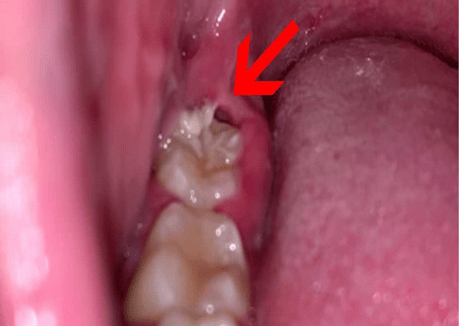

What Is an Impacted Wisdom Tooth?

An impacted wisdom tooth occurs when the tooth does not fully emerge from the gums due to lack of space.

Types of impaction include:

- Horizontal impaction

- Vertical impaction

- Partial eruption

- Fully impacted tooth

Impacted teeth can cause infection, pain, and damage to nearby teeth.